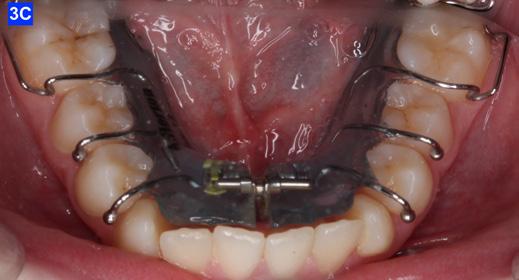

The patient was transferred to our office after 12 months of treatment with her previous clinician. She had a maxillary Hyrax, a mandibular Schwarz appliance and a partially bracketed upper arch with .022 x .028 Passive Self-Ligating (PSL) brackets (Carriere – Ortho organizers). The leveling arch wire was a .018 NiTi. The previous clinician proposed; transverse development, SWA and retention. The patient was already referred to an ENT for the evaluation of her airway. The authors explained to the patient and her mother that we may not be able to accommodate the maxillary cuspids and that odontectomy of two bicuspids may be necessary. We would, however, continue with the expansion protocol to its fullest capacity, utilize Straight Wire Appliances and add TADs to assist with translation of the maxillary cuspids. Class III elastics would be necessary and life-time retention of the dentition

following completion of the treatment. Composite add-ons were considered on maxillary lateral incisors, if required (Figure 3-A, B, C).

4-A, Figure 3A: The patient transferred to our office, frontal view Figure 3B: The patient transferred to our office, maxilla, occlusal view Figure 3C: The patient transferred to our office, mandible, occlusal view Figure 4A: OCS, frontal view Figure 4B: Hyrax, occlusal view Figure 4C: Retraction of maxillary lateral incisors